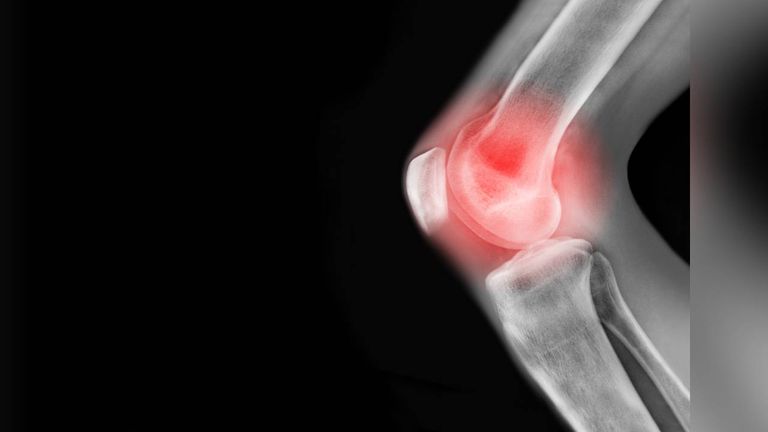

Las investigaciones se enfocan en genes y proteínas, incluidos los microARN, que podrían activar la capacidad de regeneración. Esto abriría la puerta a nuevos tratamientos y, eventualmente, a la posibilidad de regenerar extremidades humanas. Un estudio publicado en *Science Advances* en 2019 reveló que los humanos tienen la capacidad de regenerar cartílago, desafiando la creencia tradicional de que este tejido no se regenera.

Resulta mejor la replicación celular por medio de moléculas como las de la terapia de Regeneración Celular a Base de Inductores, en lugar de tratar de crear células madre en el laboratorio, abriendo con ellos nuevas posibilidades para los pacientes con lesiones articulares y artritis, permitiendo la regeneración natural del cartílago.

Las investigaciones actuales del científico mexicano no solo se centran en el cartílago, sino también en otros tejidos y órganos. Es importante señalar que la capacidad de manipular y dirigir la regeneración celular tiene el potencial de revolucionar la medicina, ofreciendo soluciones para enfermedades crónicas y degenerativas que antes se consideraban incurables. Esta terapia estimula la regeneración y reparación de tejidos dañados, mejorando la función de órganos y tejidos convirtiéndose en una excelente alternativa a los tratamientos convencionales que a menudo solo alivian los síntomas sin abordar la causa subyacente.

La Terapia de Regeneración Celular a Base de Inductores tiene aplicaciones potenciales en el tratamiento de enfermedades como la diabetes, la artritis, el cáncer y las enfermedades cardiovasculares. Al mejorar la capacidad del cuerpo para regenerarse.